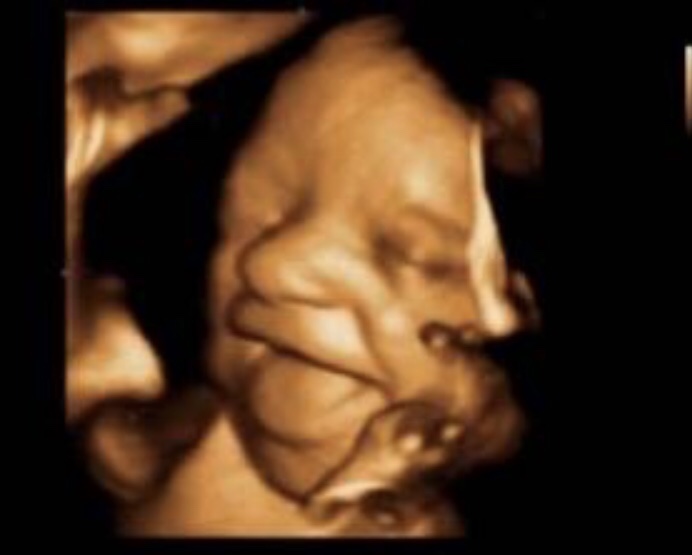

😂 на самом деле да) тоже об этом думала. Но когда увидела своего ребёнка (с первым делала 2 года назад) и она нам улыбнулась... это было нечто! Я плакала от счастья! Это самое милое что я видела до этого, ну и конечно когда родилась часто вспоминала, что она и в животике нам улыбалась 😁